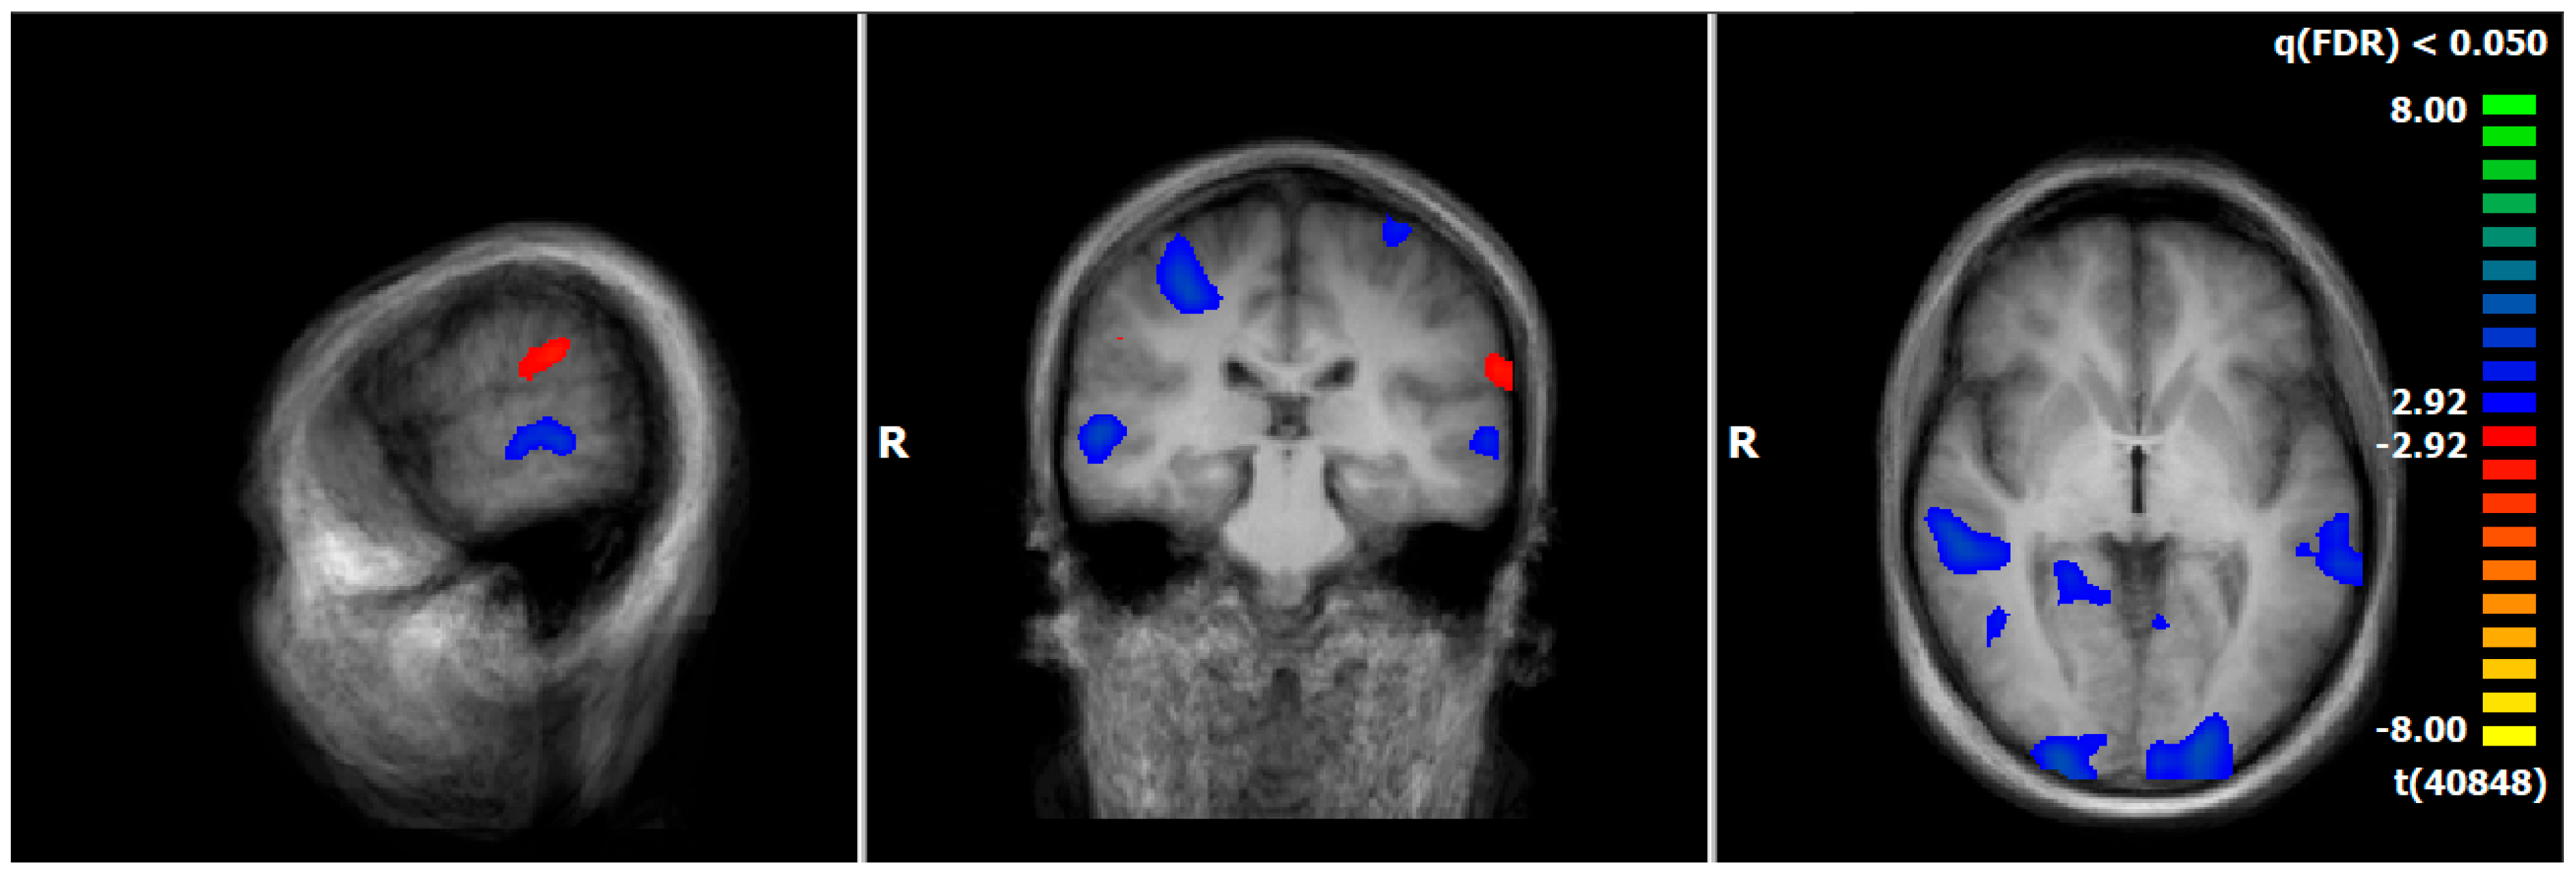

3.4. Comparison of Neuronal Responses Before and After Therapy—PPPD

3.6. HC: Pre–Post Comparison of Neuronal Responses Following a 5–6-Week Interval